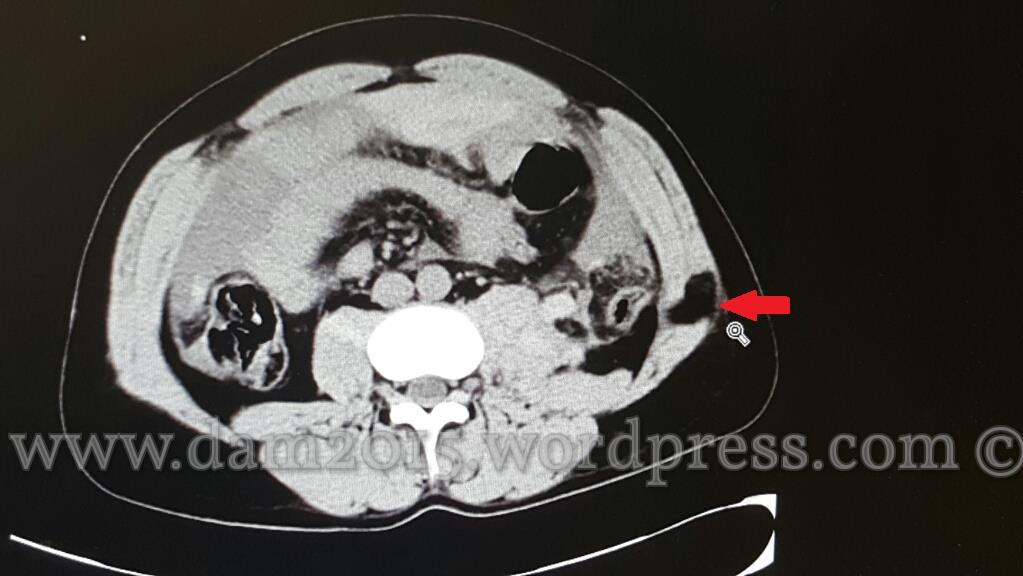

Paziente uomo, 35 anni, con ferita penetrante da arma bianca in fianco sinistro.

Addome acuto, emoperitoneo, aria libera endoperitoneale.

Presenza di bolle d’aria nel contesto del muscolo obliquo dell’addome a livello della soluzione di continuo.

Presenza di aria libera endoaddominale.

Quota fluida di versamento nello scavo pelvico.